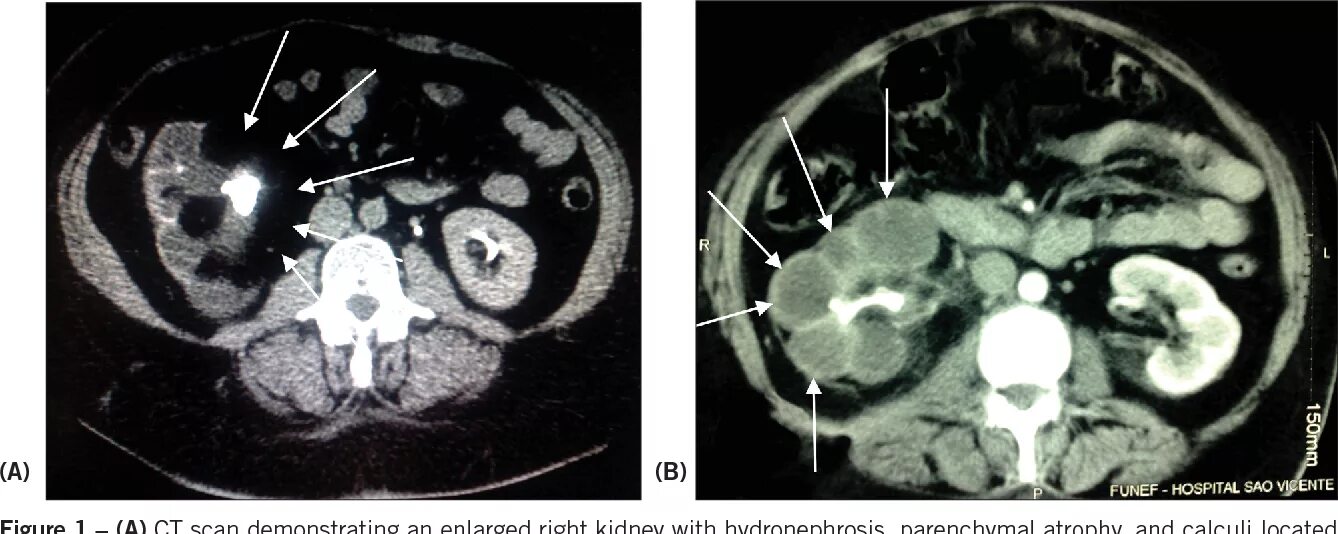

Пиелонефрит кт